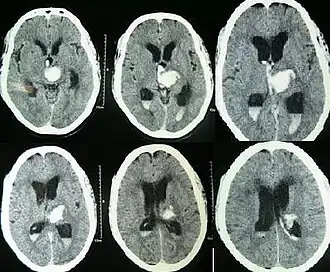

CT scan of a spontaneous intracerebral bleed, leaking into the lateral ventricles

Spontaneous ICH with hydrocephalus on CT scan[22]

Both computed tomography angiography (CTA) and magnetic resonance angiography (MRA) have been proved to be effective in diagnosing intracranial vascular malformations after ICH.[12] So frequently, a CT angiogram will be performed in order to exclude a secondary cause of hemorrhage[31] or to detect a "spot sign".

Intraparenchymal hemorrhage can be recognized on CT scans because blood appears brighter than other tissue and is separated from the inner table of the skull by brain tissue. The tissue surrounding a bleed is often less dense than the rest of the brain because of edema, and therefore shows up darker on the CT scan.[31] The oedema surrounding the haemorrhage would rapidly increase in size in the first 48 hours, and reached its maximum extent at day 14. The bigger the size of the haematoma, the larger its surrounding oedema.[32] Brain oedema formation is due to the breakdown of red blood cells, where haemoglobin and other contents of red blood cells are released. The release of these red blood cells contents causes toxic effect on the brain and causes brain oedema. Besides, the breaking down of blood-brain barrier also contributes to the odema formation.[13]

For spontaneous intracerebral hemorrhage seen on CT scan, the death rate (mortality) is 34–50% by 30 days after the injury,[22] and half of the deaths occur in the first 2 days.[52] Even though the majority of deaths occur in the first few days after ICH, survivors have a long-term excess mortality rate of 27% compared to the general population.[53] Of those who survive an intracerebral hemorrhage, 12–39% are independent with regard to self-care; others are disabled to varying degrees and require supportive care.[8]